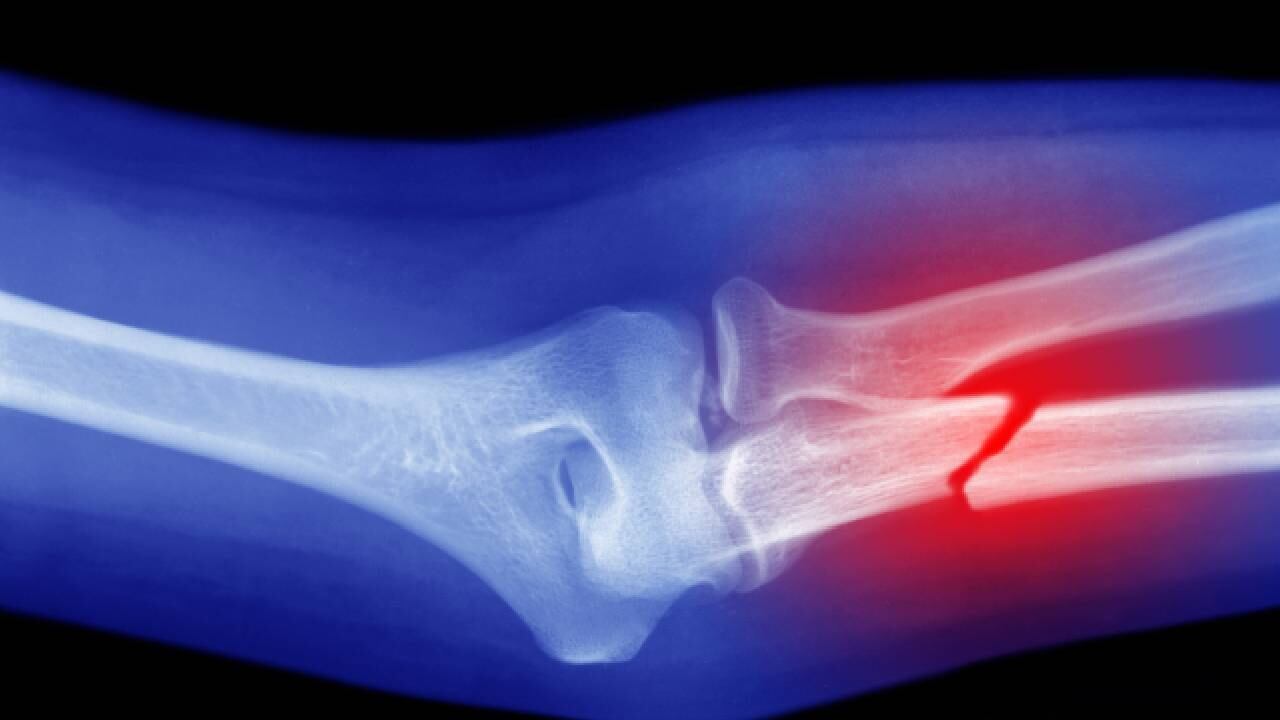

1. Debilidad ósea

La principal consecuencia de tener una debilidad en los huesos es la osteoporosis, enfermedad que hace que los huesos permanezcan débiles y frágiles, causando que sean más propensos a fracturas. Además, se puede contraer problemas de dentición.